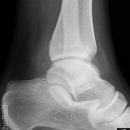

Sprunggelenk

Weber A

Weber B

Weber C + dorsales Volkmann

Trimalleoläre

Vorderes Volkmann + lat. Talusschulter